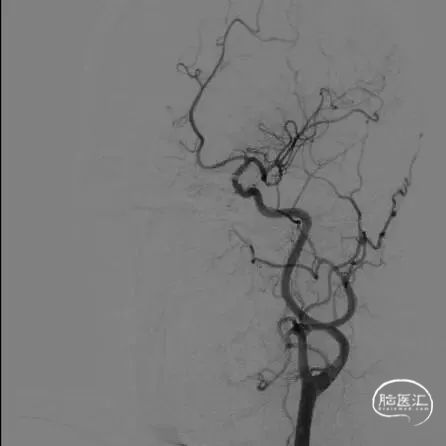

支架植入后造影及3D。

支架植入

支架植入后

术后即刻复查头颅CT未见异常。

术后定期门诊随访,1月以来患者未诉不适,头晕好转,肢体麻木感消失。